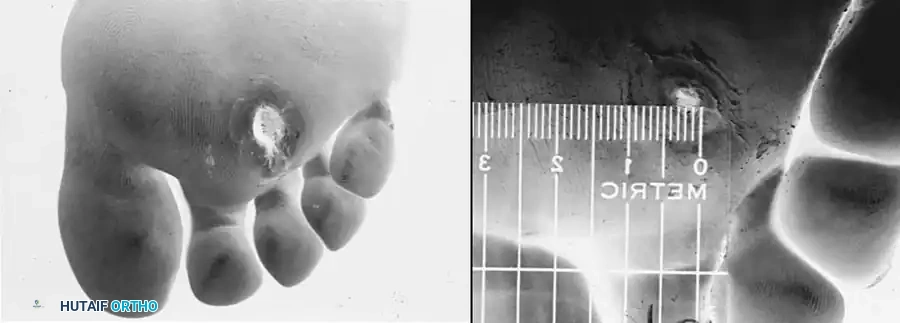

Diagnostic Pitfalls: Thermal Injuries vs. Gangrene

Patients with profound sensory dysesthesia often resort to dangerous methods to warm their perceived "cold" feet. This can result in severe thermal injuries that mimic ischemic gangrene.

Fig. 82-12: "Gangrenous" changes at the tips of the toes. These were, in fact, deep burns secondary to a "cold" dysesthetic foot being placed too close to a space heater for warmth. These wounds eventually healed with conservative care and do not represent a true example of a Wagner grade 4 ischemic lesion.

Surgical Warning: Always take a meticulous history regarding the use of heating pads, hot water soaks, or space heaters in patients presenting with acute, black, eschar-covered lesions on the digits. Misdiagnosing a thermal burn as dry gangrene can lead to unnecessary and premature amputation.